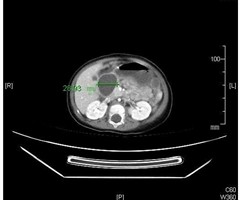

[摘要] 目的 探讨中性粒细胞与淋巴细胞比值(NLR)、降钙素原(PCT)与改良CT严重指数评分(MCTSI)联用对重症急性胰腺炎(SAP)继发感染性胰腺坏死(IPN)的早期预测价值。方法 分析324例SAP病人的临床资料,根据是否发生IP...